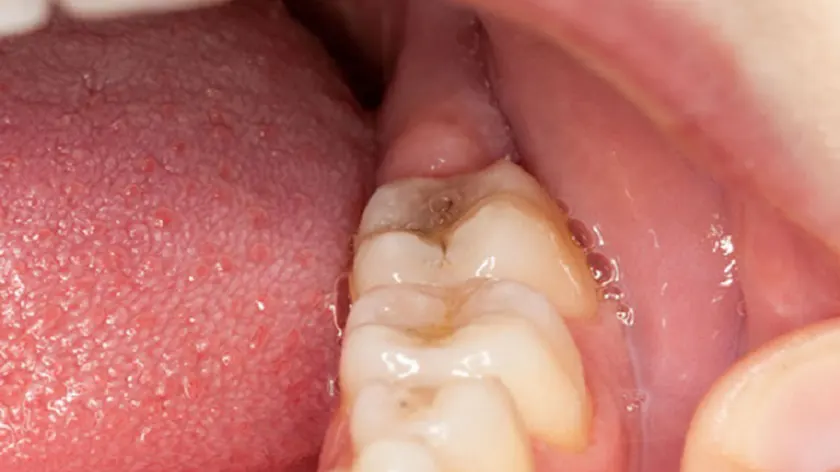

Viêm nướu răng khôn là tình trạng nướu quanh răng khôn vị viêm nhiễm. Răng khôn nằm sâu trong cùng và mọc từ khoảng 17 – 25 tuổi. Do đó, răng khôn dễ mọc ngầm, mọc lệch và gây đau nhức khó chịu.

Viêm lợi trùm răng khôn xuất hiện khi răng mới nhú, chúng ta có thể quan sát bằng mắt thường. Thời gian mọc răng khôn kéo dài, phần mô mềm trùm lên răng lâu ngày có thể khiến thức ăn sót lại và vi khuẩn tích tụ nếu không vệ sinh răng miệng đúng cách. Viêm nướu răng khôn thường xuất hiện ở răng khôn hàm dưới.

Theo các chuyên gia, không phải ai mọc răng khôn cũng gặp tình trạng này. Viêm nướu răng khôn có thể nhận biết thông qua các triệu chứng sau:

- Nướu răng, đỏ và chảy máu.

- Ăn không ngon, miệng xuất hiện mùi vị khó chịu.

- Sưng hạch bạch huyết ở hàm dưới.

- Cứng hàm, khó khăn trong việc mở miệng và ăn uống.

- Tế bào bạch huyết của hệ miễn dịch ở dưới nướu bị viêm nhiễm và có mủ.